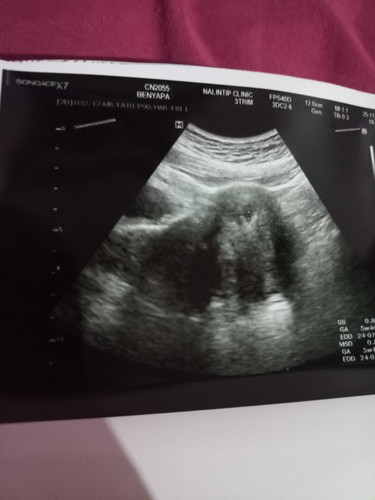

วันนี้ไปหาหมอฝากครรภ์มาค่ะ5W4Dยังดูไม่ออกเลยค่ะแม่ๆช่วยดูหน่อยค่ะ

ในจุดไข่ปลาขาวๆเล็กๆ 2 จุดนั่นคือถุงการตั้งครรภ์ค่ะแต่ว่ายังไม่เห็นตัวน้อง